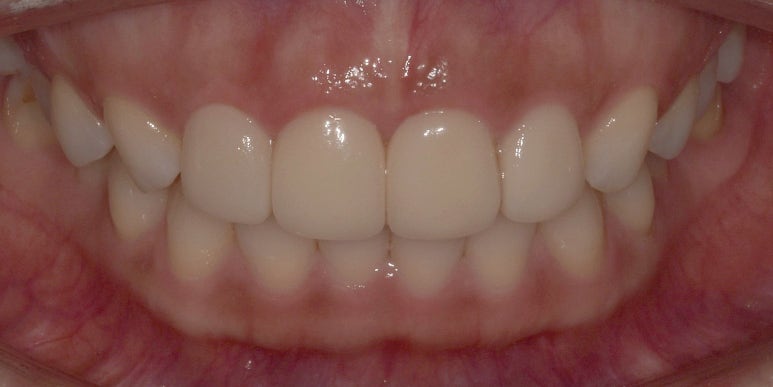

이제 라미네이트를 최종적으로 부착하고 나서 한달 정도 지난 후의 사진을 보여드리겠습니다.

라미네이트 부착 후 약 1개월 정도 지난 후의 모습

2023-06-28

저는 지금 치아 색상보다 살짝 밝게 라미네이트를 제작해달라고 요청드렸어요.

왜냐하면 주기적으로 미백을 할 예정이기 때문에

지금보다는 살짝 밝아도 될 것 같았기 때문입니다!

너무 자연스러운 색상 아니냐고 하실 수도 있는데

저는 자연스러운게 더 좋아서 이 톤으로 진행하게 됐어요.

라미네이트, 잇몸성형, 치아미백 치료 전후 비교 사진

(치료 전) 2023-05-10 (치료 후) 2023-06-28

어떠신가요? 전후를 놓고 비교해보니 틀어져있던 앞니가 바로잡혔고,

조금 작았던 양 옆 치아도 앞니와 어우러지는 사이즈로 변하면서 더욱 고르게 변한 모습이죠?